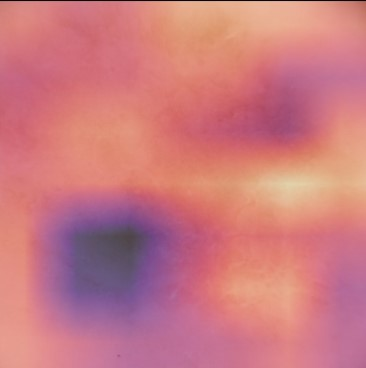

State-of-the-art deep learning approaches for skin lesion recognition often require pretraining on larger and more varied datasets, to overcome the generalization limitations derived from the reduced size of the skin lesion imaging datasets. ImageNet is often used as the pretraining dataset, but its transferring potential is hindered by the domain gap between the source dataset and the target dermatoscopic scenario. In this work, we introduce a novel pretraining approach that sequentially trains a series of Self-Supervised Learning pretext tasks and only requires the unlabeled skin lesion imaging data. We present a simple methodology to establish an ordering that defines a pretext task curriculum. For the multi-class skin lesion classification problem, and ISIC-2019 dataset, we provide experimental evidence showing that: i) a model pretrained by a curriculum of pretext tasks outperforms models pretrained by individual pretext tasks, and ii) a model pretrained by the optimal pretext task curriculum outperforms a model pretrained on ImageNet. We demonstrate that this performance gain is related to the fact that the curriculum of pretext tasks better focuses the attention of the final model on the skin lesion. Beyond performance improvement, this strategy allows for a large reduction in the training time with respect to ImageNet pretraining, which is especially advantageous for network architectures tailored for a specific problem.

翻译:在皮肤损伤识别方面,最先进的深层学习方法往往要求就更大规模、更多样化的数据集进行预先培训,以克服因皮肤损伤成像数据集规模缩小而产生的一般限制。图像网通常用作预培训数据集,但其转移潜力受到源数据集和目标皮肤科情景之间领域差距的阻碍。在这项工作中,我们采用新的预培训方法,按顺序培训一系列自我监视学习的借口任务,只要求不贴标签的皮肤损伤成像数据。我们提出了一个简单的方法,以建立一个命令来界定一个托辞任务课程。对于多级皮肤损伤分类问题和ISIC-2019数据集,我们提供了实验性证据,表明:一) 由一个托辞任务课程比个人托辞任务预先训练的模式更优于模型,这在图像网上培训模型比模型先培训更优于模型。我们证明,这一业绩收益与以下事实有关:一个更突出托辞任务的重点,即界定一个托辞任务课程,确定一个托辞任务大纲。对于多级皮肤损伤分类问题,以及ISIC-2019数据集,我们提供了实验性地证明:一模型预设的模型的模型预设型模型预训练模型,使得最终的升级模型能够改进。